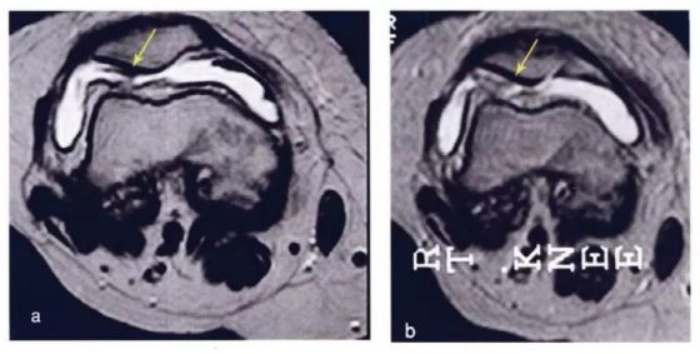

·研究结果:关节内注射骨髓间充质干细胞6个月后,,疼痛、、、功能状态和步行距离均提高。。。6名治疗组中3名患者在治疗前后的MRI比较可以看出,,该治疗对于改善软骨厚度,,,,修复组织延伸超过软骨下骨,,,,以及减少软骨下骨的水肿是非常显著的。。

下图a示意治疗前软骨,,,b为治疗后6个月软骨,,,,箭头所示为软骨修复位置。。。